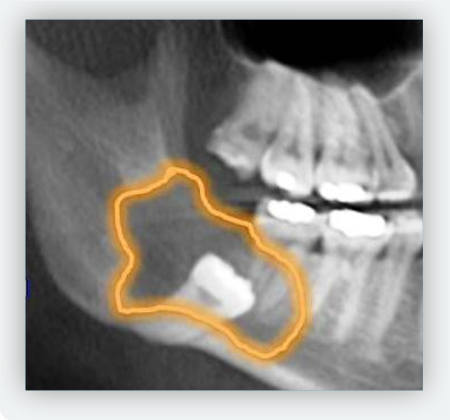

- Están retenidas o impactadas

- Existe riesgo de daño óseo

- Quistes o problemas óseos

Lo primero que debes hacer es agendar una cita de valoración con nuestro especialista en cirugia oral y maxilofacial; el Dr. Felipe Naranjo, el realizará una valoración clínica de tu caso, y con la ayuda de radiografias realizará la extracción de las piezas en caso tal que sea necesario. La extracción de muelas cordales es un procedimiento seguro, realizado bajo anestesia local, con técnicas modernas que minimizan el dolor y aceleran la recuperación.